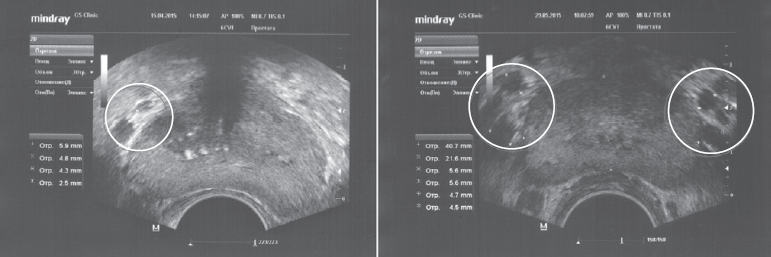

Полученные А.А. Капто и др. (2016) данные свидетельствуют о том, что обнаружение расширенных вен парапростатического сплетения по данным ТРУЗИ указывает на наличие варикоцеле и связанного с ним венозного полнокровия простаты. При этом варикоз простаты всегда выявляется на стороне варикоцеле и может быть ипсилатеральным при одностороннем варикоцеле и билатеральным при двустороннем (рис. 18). Это позволяет определить варикоцеле как причину не только гипотрофии яичка и патоспермии, но и тазовых нарушений, связанных с венозным полнокровием [59].

Рис. 18. ТРУЗИ предстательной железы у пациентов с левосторонним (слева) и двусторонним варикоцеле (справа). Отмечается варикозное расширение вен парапростатического венозного сплетения на стороне локализации варикоцеле